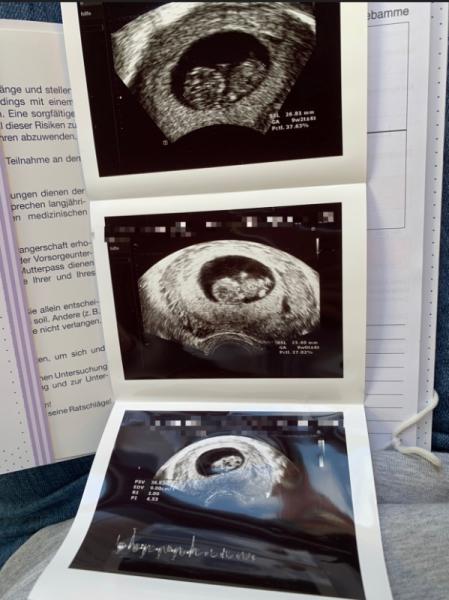

Ich war gestern auch bei der ersten Sono.. das war eine so große Erleichterung!! Und mein Mann musste tatsächlich ein Tränchen verdrücken als uns die FÄ gezeigt hat, wie das kleine rumhüpft

Bild zu

Wow echt schöne ultraschallbilder, und schön das bei dir auch alles in Ordnung ist. Ich kann es auch noch kaum abwarten bis zum 17.9